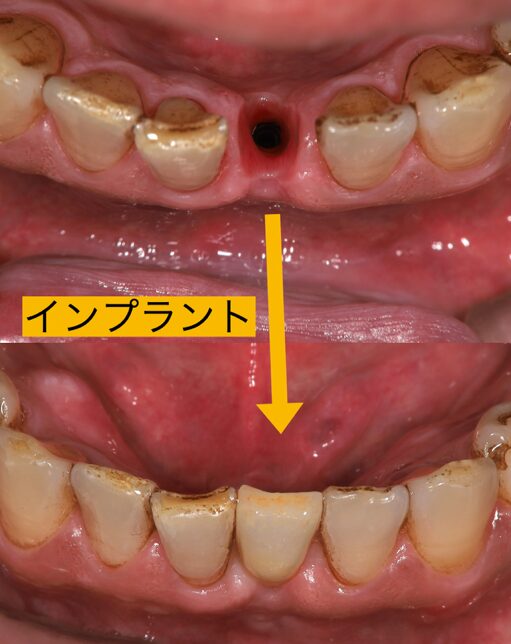

抜いてその日にインプラントを入れる抜歯即時インプラントの術式を選択しました。シミュレーションを行いデンサーバーという特殊なバーで骨質改善を行い、骨を硬くしてインプラントを埋入することになりました。

インプラント手術は抜いたその日に入る抜歯即時埋入で行いました。抜歯はすぐに終わったのですが、膿がかなりあり掻爬に時間がかかりましたが、ここをおろそかにするわけにはいきません。しっかりと膿取りを行い、デンザーバーで形成し細い2.8ミリのインプラントを埋入しました。

メリットは歯を抜く事とインプラントを埋入する手術が一度にできる、痛みも少ないなどがありますがその反面、膿があったところにインプラントを入れるので感染のリスクもあります。よって歯を抜いた後の膿取りをしっかりおこなう事や掻爬をしっかりと行う必要があります。そして、膿があったということは骨が吸収していることが多く、残存骨がないとインプラントを固定できません。さらに歯を抜いた部位は骨が活性化して柔らかくなります。よって当院ではデンサーバーという骨を硬くできる特殊なドリルを用いて残っている健康な骨を分析の段階でしっかりと見極めて安全に、性格にインプラント治療を行います。その際にはサージカルガイドや位置を決定するサージカルガイドやプロビガイドを使用します。